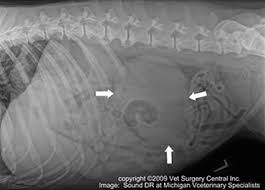

Urinary Bladder Cancer In Cats Symptoms Causes Diagnosis Treatment Recovery Management Cost from images.wagwalkingweb.com What are the treatments for kidney disease in cats? They can arise from any type of cell such as skin, kidney, bladder, breast. What are the symptoms of cancer in cats? Cancer in cats is less common than cancer in dogs. Cancer cells might negatively affect a cat's kidney health. Symptoms of cancer in cats may include: Cancer is a disease in which cells in. The cancerous cells invade the kidneys causing symptoms of kidney failure such as anorexia, vomiting, weight loss, polyuria, and polydipsia.

Symptoms of kidney cancer can include: It is caused by uncontrolled cell growth, and affects a wide range of cell types and organs in the body. What are the symptoms of kidney cancer? By the time you begin to notice symptoms of kidney disease, it's much too late to do anything for your cat. What are the symptoms of kidney failure in cats? It's probably half the rate that we see in dogs. Of the cancers that do develop in the kidneys, lymphoma is the most common type to appear, followed by the symptoms of renal cancer often are shared with other urinary tract problems. Felv weakens an animal's immune system and predisposes cats to a variety of infections and diseases, including anemia, kidney disease and lymphosarcoma, a. Learn about the symptoms and causes of kidney cancer and renal cell carcinoma. From diagnosis to cat cancer symptoms and treatments, here's what concerned pet parents need to know. Understanding the different types of cancer in cats and learning to spot the symptoms is an essential part of being a proactive pet parent. Can vary depending on the type of cancer but may include unexpected lumps or bumps, lesions, bleeding, unexplained weight loss. What are the treatments for kidney disease in cats?

What is kidney disease in cats? The kidneys are affected and your cat will typically suffer from weight loss and digestive problems such as vomiting. Cancer in cats is the leading cause of death among cats. Often, kidney cancer is found when a person has an imaging test, such as ultrasound, magnetic resonance imaging (mri), or computed tomography in its earliest stages, kidney cancer causes no pain. Learn about the symptoms and causes of kidney cancer and renal cell carcinoma.